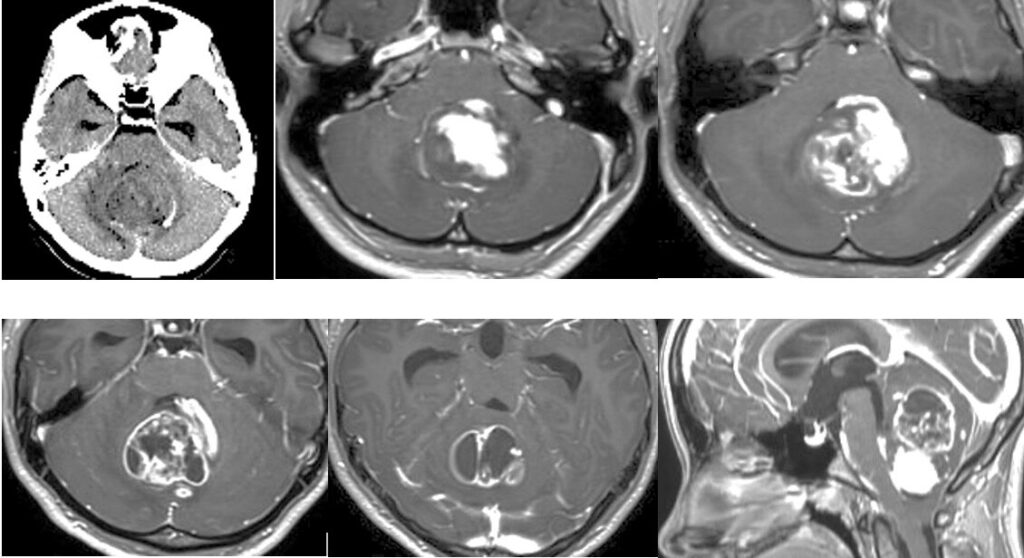

72歳男性 延髄脳幹部海綿状血管腫オペ